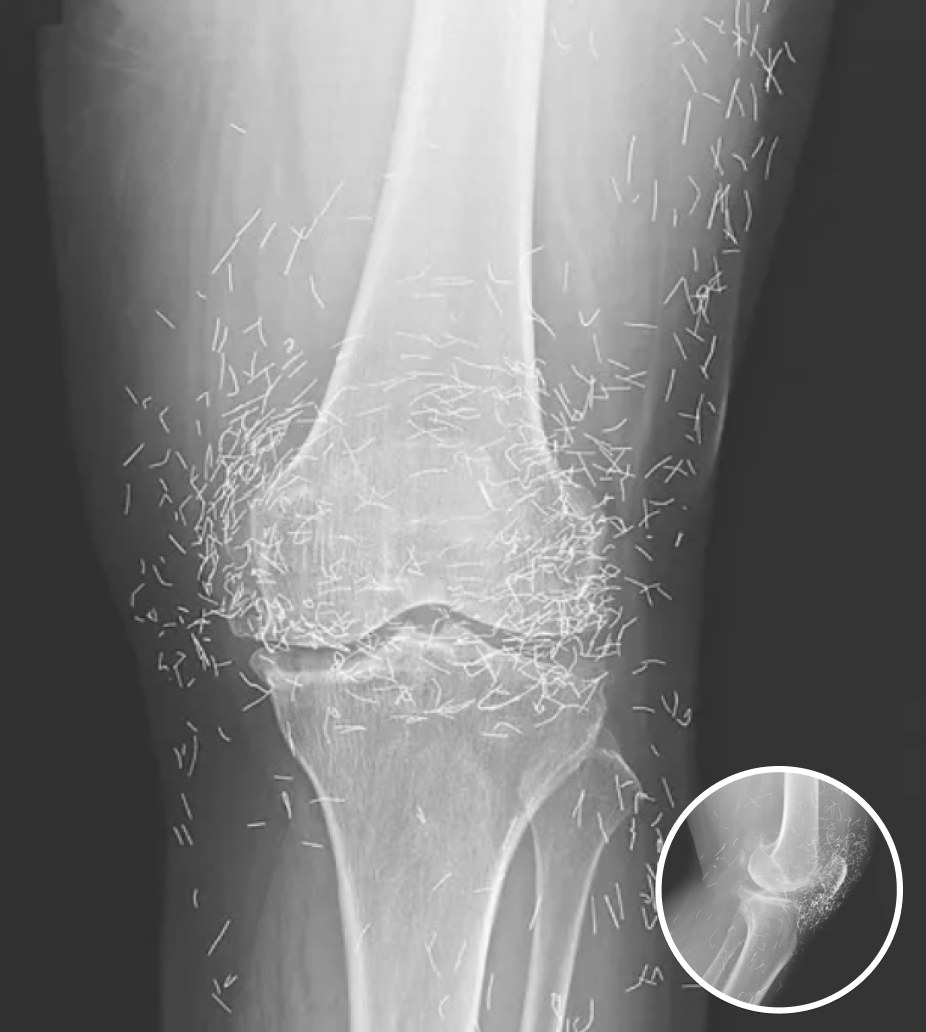

Eine routinemäßige Röntgenuntersuchung der Knie einer 65-jährigen Frau mit starken Gelenkschmerzen brachte eine unerwartete Überraschung ans Licht. Was die Ärzte fanden, war schlichtweg erstaunlich: Hunderte winziger Goldnadeln, die tief in ihrem Gewebe eingebettet waren.

Akupunktur, eine traditionelle, in Asien weit verbreitete Therapieform, besteht darin, dünne Nadeln in bestimmte Punkte des Körpers einzuführen, um Schmerzen zu lindern oder Krankheiten zu behandeln. In diesem Fall jedoch, so die Ärzte, wurden die Goldnadeln absichtlich im Rahmen ihres Behandlungsplans belassen, um die betroffene Stelle kontinuierlich zu stimulieren.

Es gibt weitere Komplikationen. Im Gewebe steckende Nadeln können die Bildgebung beeinträchtigen. „Sie können Teile der Anatomie auf einem Röntgenbild verdecken“, bemerkte Guermazi. Noch alarmierender ist, dass Patienten mit Metallfragmenten im Körper niemals eine MRT-Untersuchung durchführen lassen sollten, da die Magnetkraft die Nadeln verschieben und dadurch möglicherweise Blutgefäße verletzen und lebensbedrohliche Schäden verursachen könnte.

Eine Röntgenaufnahme des Knies des Patienten zeigt im Gewebe eingebettete Akupunkturnadeln. Bildquelle: Reddit

Der Fall der Südkoreanerin wurde kürzlich im New England Journal of Medicine dokumentiert. Auch wenn die Nadeln möglicherweise zur Linderung ihrer Beschwerden gedacht waren, zeugen ihre Röntgenbilder von den potenziellen Risiken extremer alternativer Therapien.